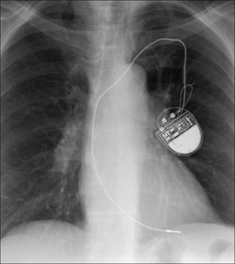

image

Figure 12.7 Optimal electrode position. Single chamber pacemaker. The ventricular lead has its tip situated at the apex of the right ventricle. (Retouched.)